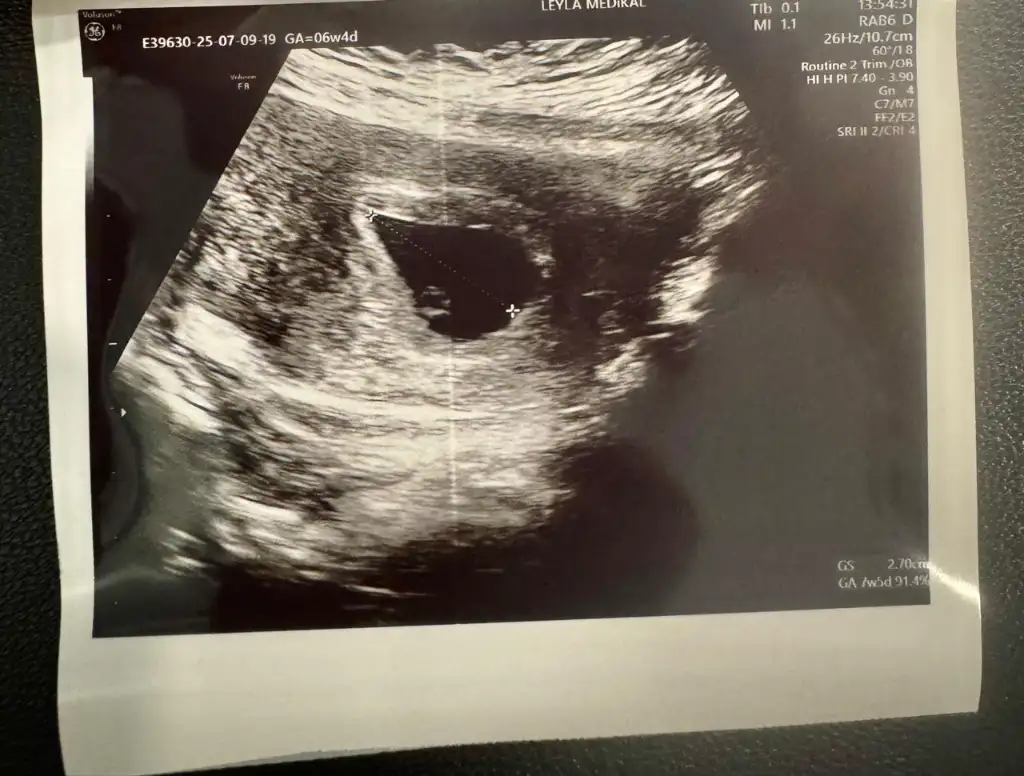

Lütfen bana bakarmısınız,? 6 hafta 4 gunluk bebisim